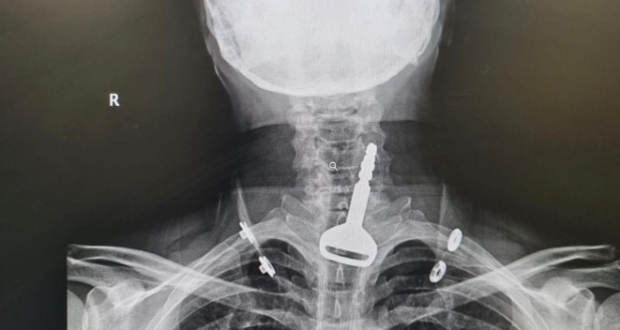

نجح فريق طبي بمدينة القنفذة (غرب السعودية) من استخراج مفتاح سيارة عالق بالجهاز التنفسي لمريض اربعيني كاد أن يودي بحياته، في عملية سريعة استغرقت 15 دقيقة عن طريق المنظار.

وأكدت الصحة السعودية أن الفرق الطبية تمكنت الثلاثاء 11 يوليو من إنقاذ حياة مريض يبلغ من العمر 49 عاما وصل لقسم الطوارئ وهو يعاني من انسداد بمجرى التنفس، حيث اتضح بعد إجراء الفحص السريري والأشعة وجود مفتاح سيارة عالق في القصبة الهوائية.

المريض الذي اعترف للأطباء بأنه كان يلهو بالمفتاح في فمه، ابتلعه عن طريق الخطأ، مما تسبب له في حالة اختناق جزئي، تطلبت التدخل الجراحي عن طريق المنظار لاستخراج الجسم المعدني العالق. ويخضع المريض الذي اتضح أنه يعاني من أمراض في القلب بقسم التنويم لحين استقرار حالته الصحية وخروجه لإكمال فترة النقاهة بمنزله.